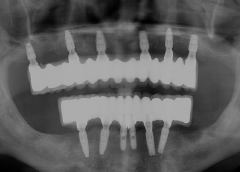

• Tình trạng mất răng:Mất toàn bộ răng hàm trên, từng mang hàm tháo lắp.

• Phương hướng điều trị:Phục hình lại toàn bộ hàm trên bằng phương án cấy ghép Implant All On 6. Cắm 6 trụ Implant và phục hình hàm sứ cố định.

• Trụ Imlant sử dụng:Implant Straumann Thụy Sỹ và răng sứ Zirconia Đức.

• Cấy ghép 6 trụ implant hàm trên loại Implant Straumann Thụy Sỹ

• Phục hình răng sứ Zirconia Đức